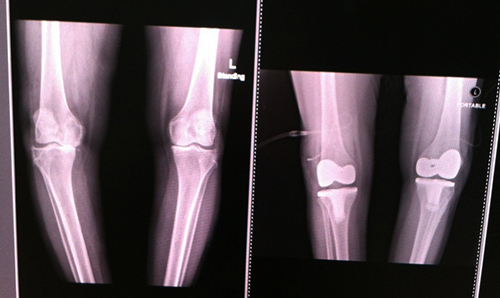

พอไปถึงก็จับเอ็กซ์เรย์ เพื่อรอแผ่นฟิล์มให้คุณหมอตรวจดู อาการเข่าเสื่อมของแม่ ก็พบว่าข้างขวาเสื่อมแน่ ๆ ส่วนข้างซ้าย ก็มีอาการเสื่อมแต่น้อยกว่า ตัดสินใจผ่าทีเดียวทั้งสองข้าง การผ่าตัดมีทั้งเปลี่ยนเฉพาะบางส่วน และเปลี่ยนเต็มข้อ สำหรับของแม่จัดเต็มข้อทั้งสองข้างเลยทีเดียว

ฟิล์มเอ็กซเรย์ก่อน (ภาพซ้าย) และหลัง (ภาพขวา) ของการผ่าตัดข้อเข่าเทียม ส่วนก้อนสีขาว ๆ ของภาพทางขวามือ คือข้อเข่าเทียมที่ใส่เข้าไป